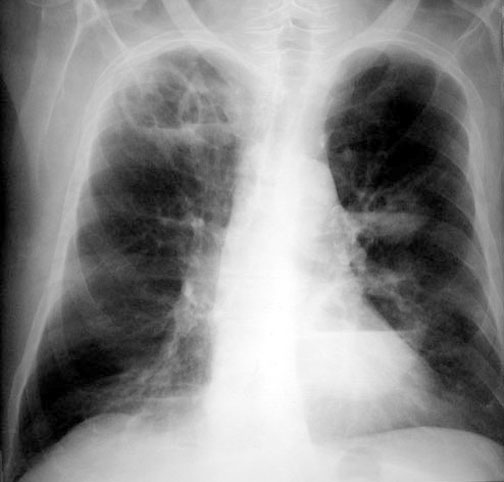

weekly clinical round for undergraduate from 8 to 11 AM during which interpretation of CHEST X rays was done for all cases of cardiothoracic surgery, gived by 2 staf member for 3 months